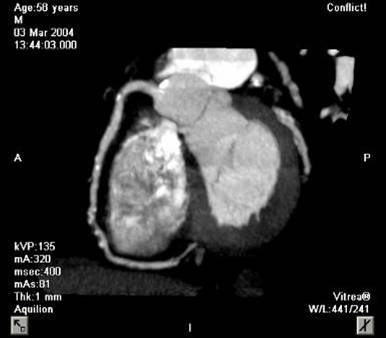

The non-invasive imaging modality of multi-detector computed tomography has dramatically evolved the last ten years and that is due to hardware and software developments. The newer generation of scanners allows increased spatial and temporal resolution that improves the clinical reliability giving further insights into the evaluation of coronary artery disease. Heart morphology imaging followed by studies of myocardial function and assessment of cardiac valves can be performed from the information derived from the data of the coronary artery examination. Also, the venous anatomy of the heart, coronary artery bypass grafts, stents, and cardiac tumors can be imaged and evaluated when necessary. For the beneficial use of this method, entrance criteria for different patient groups need to be set in order to allow improved outcome of multi-detector CT.